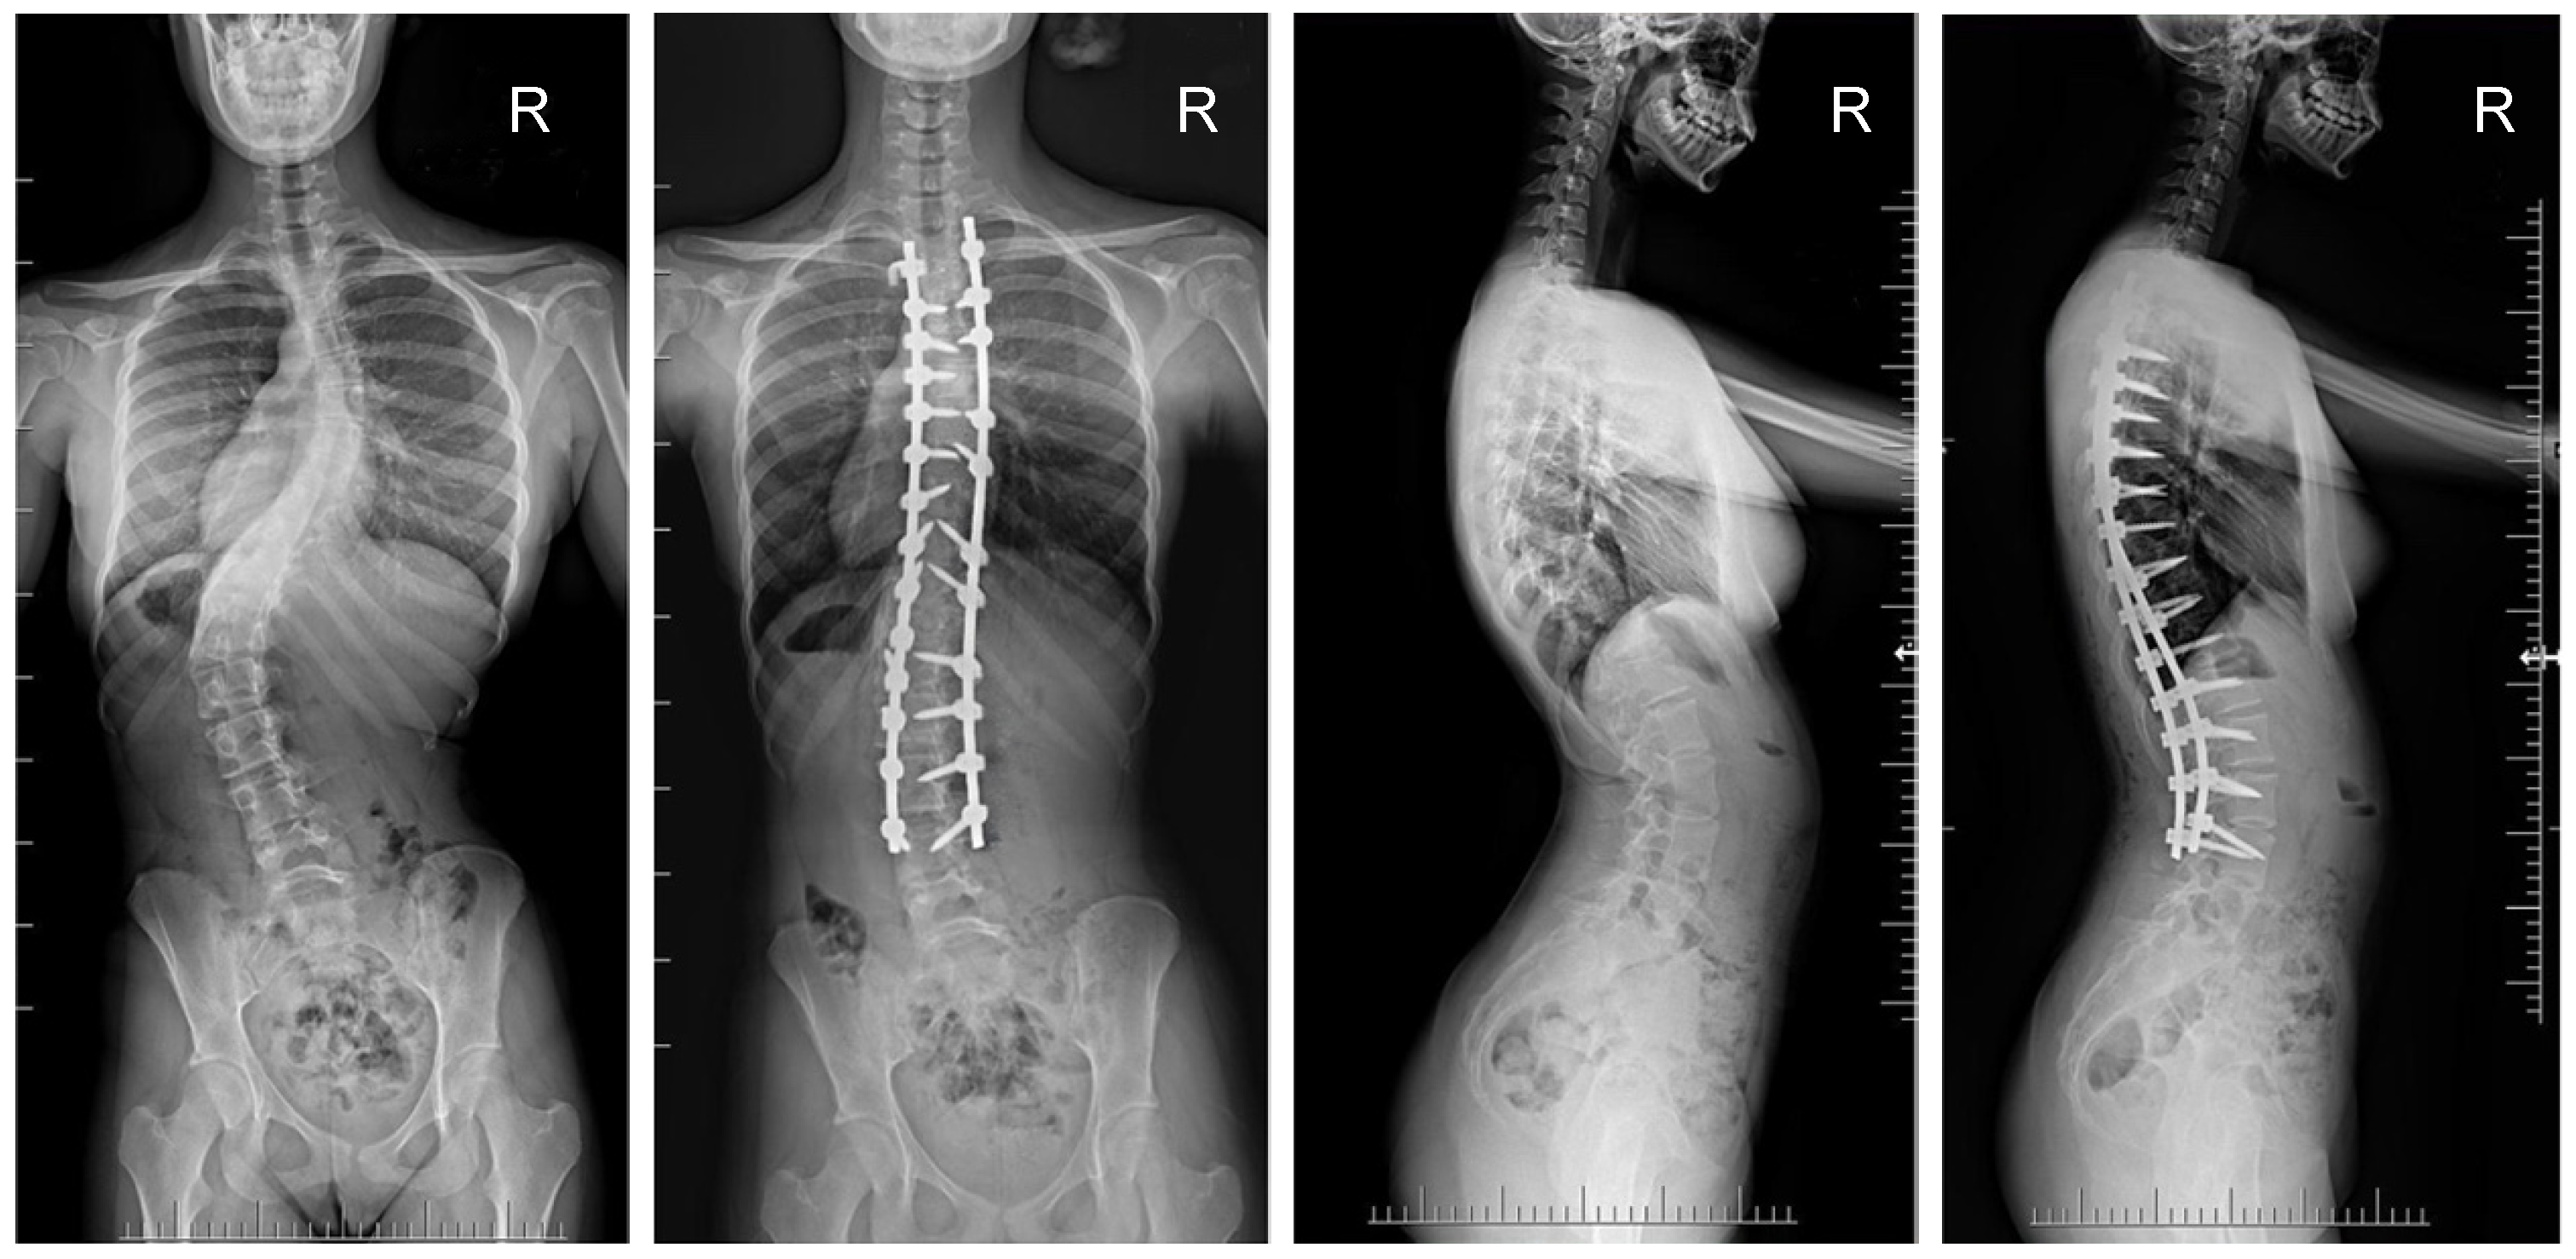

Figure 2.

X-rays of a 16-year-old girl with AIS, treated with selective thoracic fusion. A smaller (standard) screw size of 5.5 mm and 2 titanium rods of 5.5 mm (G1) were used. X-rays show curve before surgery and correction after surgical treatment.